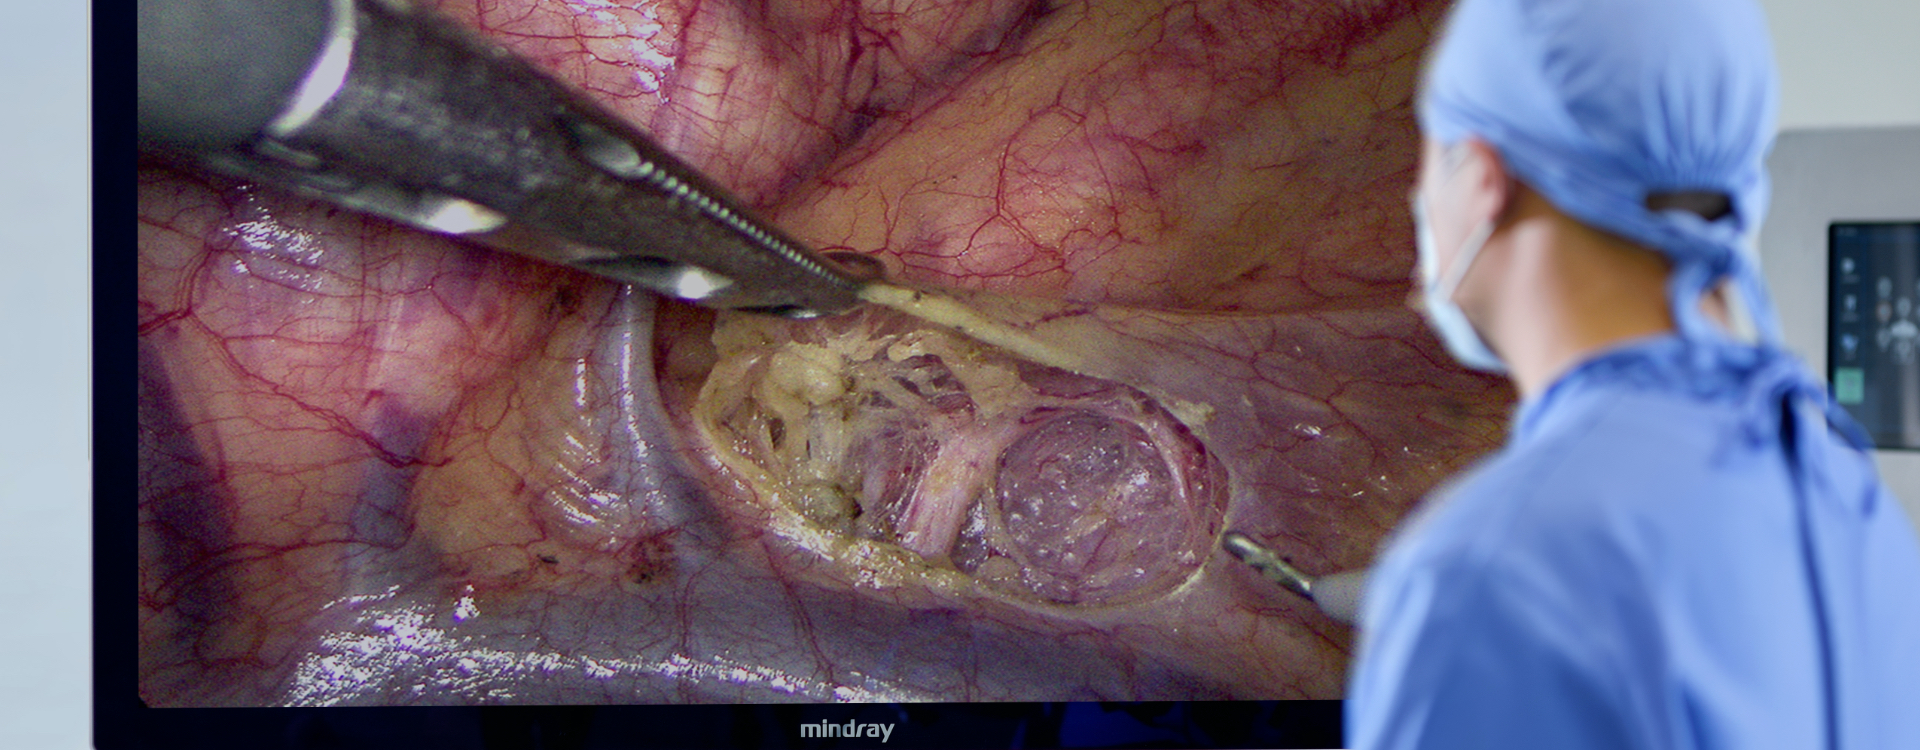

4K-resolutie

Ultra-high-definition beeld met een resolutie van 3840├Ś2160.

Breed kleurengamma

Herstel van de echte kleur van organen en weefsels, perfecte identificatie van bloedvaten, lymfeklieren en zenuwen.

3-200 mm velddiepte

Scherpstelling blijft duidelijk bij het schakelen tussen meerdere bedieningssc├©nes.

55 inch indrukwekkende ervaring

Het chirurgische beeld wordt vergroot zonder de resolutie te verminderen, zodat de details niet langer klein zijn en de visuele vermoeidheid van de arts wordt verminderd.